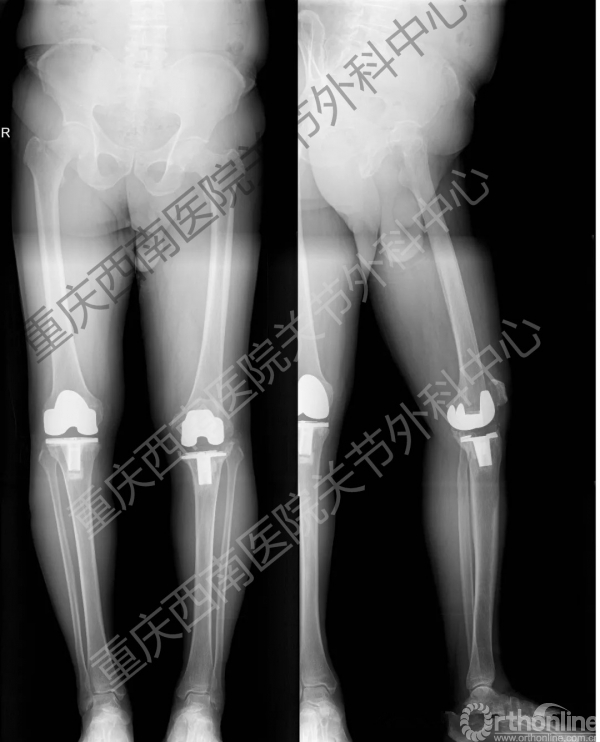

全膝关节翻修术前